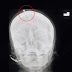

Autoridades buscam por curandeiro que deu o falso conselho à mulher. Prego não atingiu o cérebro da gestante. Ato desesperado se deve ao fato de marido ter ameaçado deixá-la por já ter três filhas.Autoridades da cidade paquistanesa de Peshawar procuravam nesta quarta-feira (09/02) um falso curandeiro que aconselhou uma mulher grávida a martelar um prego na testa para que pudesse dar à luz um menino.

Embora o prego tenha penetrado o crânio da mulher, não atingiu o cérebro, informou o neurologista Haider Suleman, que tratou a vítima no Hospital Lady Reading.

O incidente chamou a atenção das autoridades depois que o raio-x da vítima se tornou viral. A polícia examinou o conteúdo para o caso.